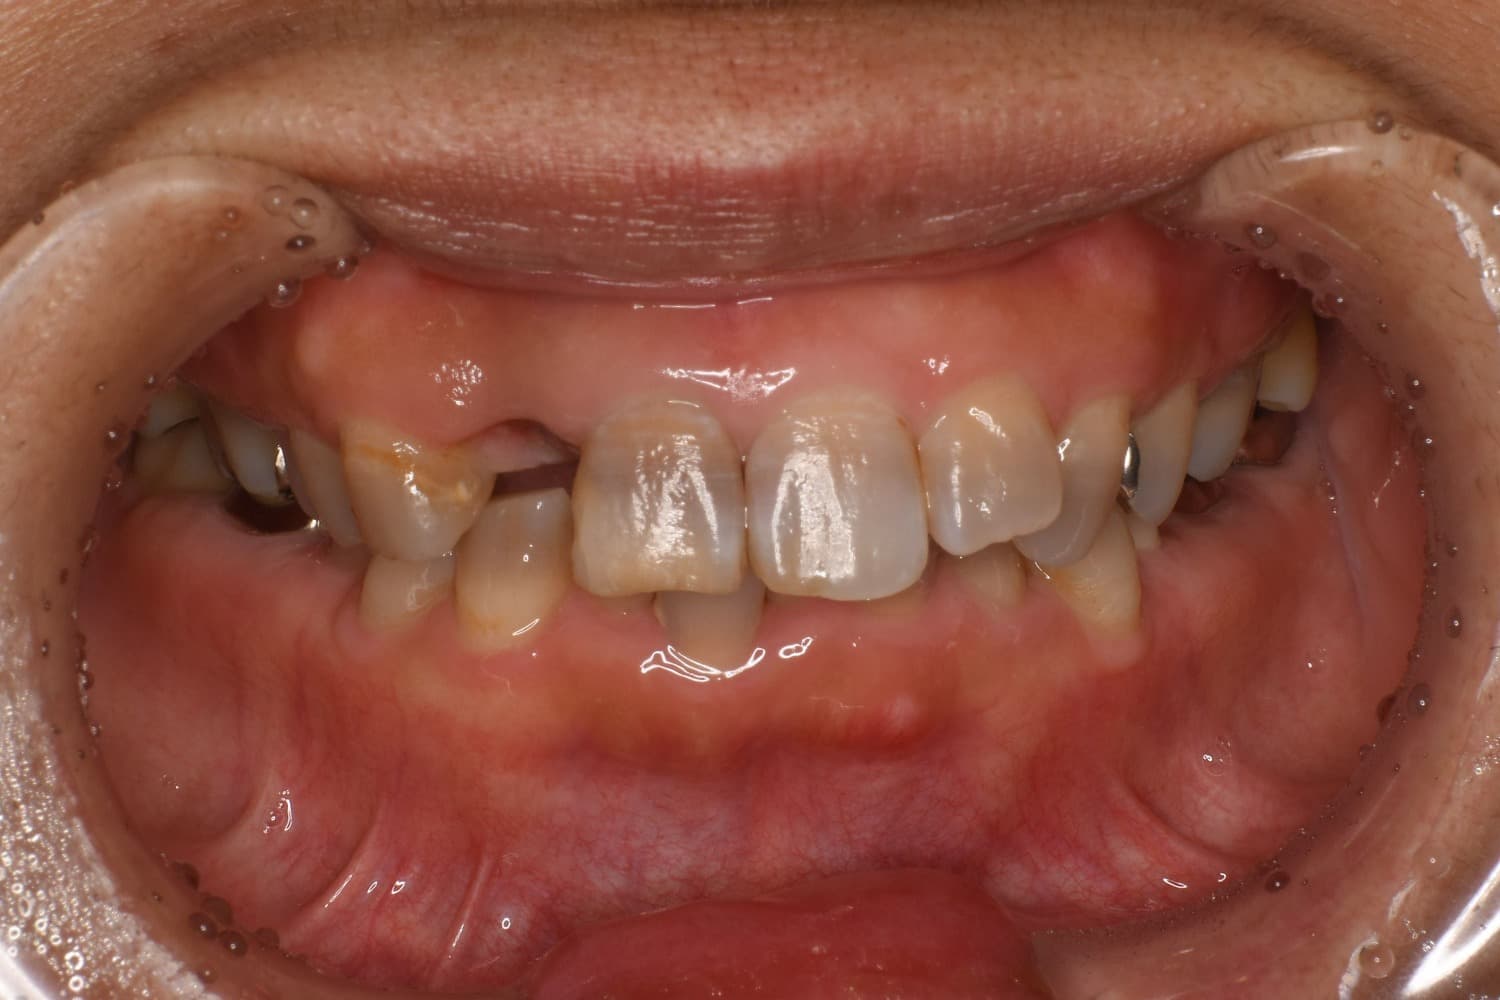

右上前歯のインプラント治療(40代女性)

Before

右上2番目の歯が縦に割れていたので抜歯をして、インプラントによる治療をおこなう。

年齢

40代

性別

女性

主訴

3日前から右上の前歯がズーンと重く痛い。

治療期間

約6ヵ月

治療回数

8回

費用

510,000円(税込み561,000円)

副作用・リスク

・治療後のメンテナンスが必要 ・清掃不良によるインプラント周囲炎 ・咬合力の強さによる被せ物の脱離や破損